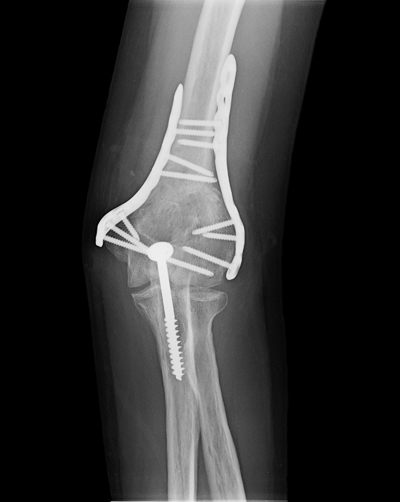

Treatment

Nondisplaced fractures usually do not require surgery and can be treated using a sling, cast, or splint. Casts are typically used in children for these fractures, as they run a lower risk of developing elbow stiffness. Displaced and unstable fractures, meanwhile, are more likely to require surgery. A surgical procedure might remove bone fragments, or replace and stabilize fragments. Open fractures will absolutely require an immediate surgical procedure to clean the wound and bone, and to minimize the risk of infection.